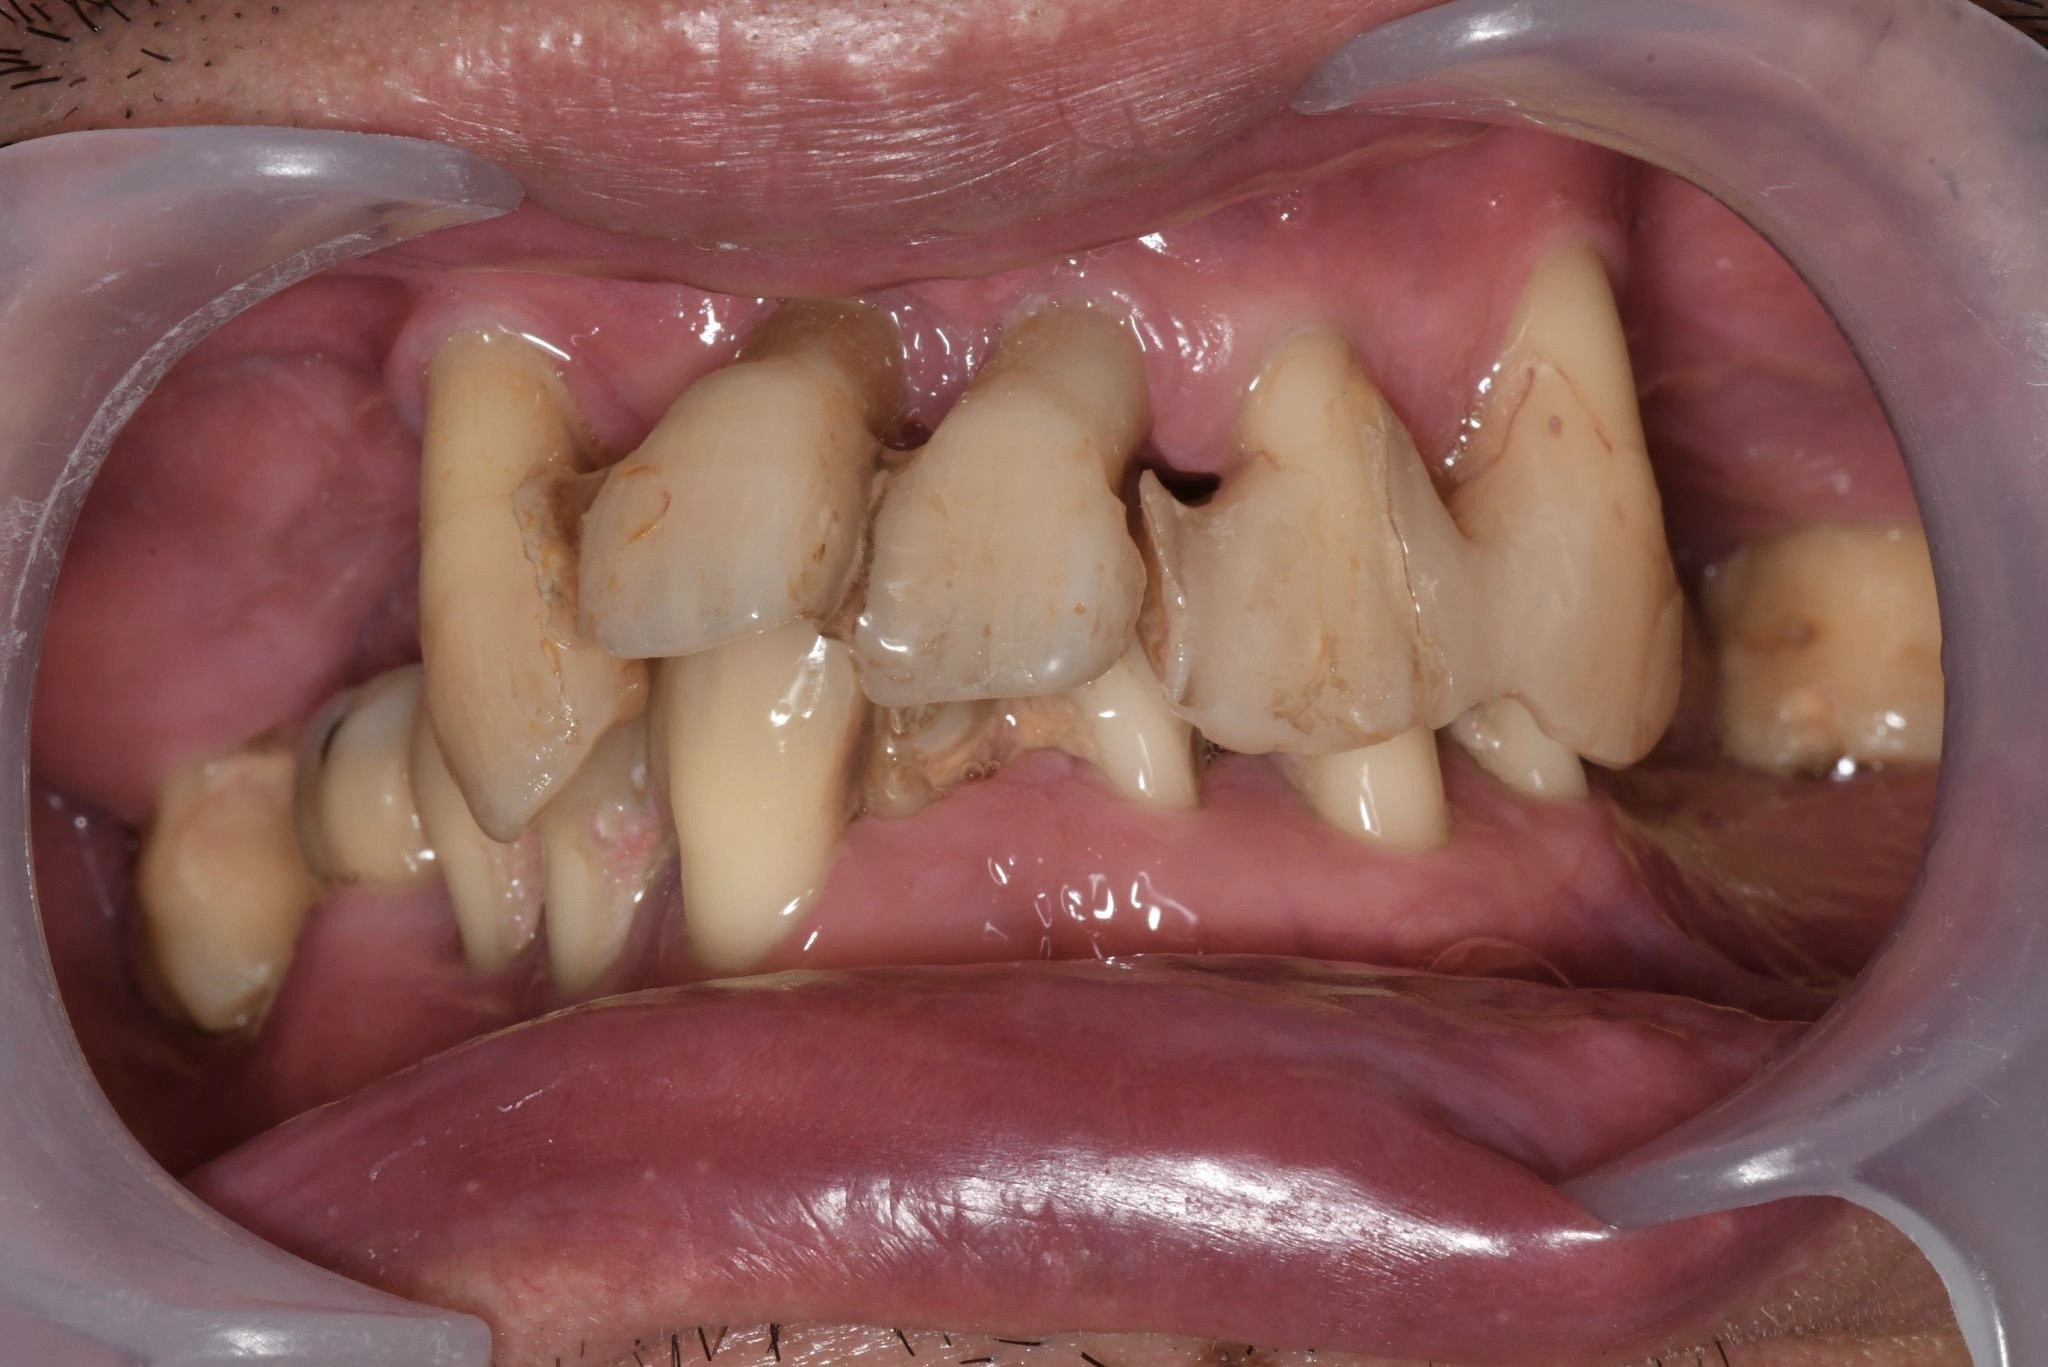

術前

内容 :上下顎オールオン4ザイゴマ4

費用 :5,230,500円

※モニター価格

期間 :半年

リスク:出血・腫れ・痺れ・痛み

以前から歯の悩みがあり、他院で入れ歯を作りましたが合わず、食事も楽しめなくなりました。歯を抜くなど治療を続けてはいたものの、改善せず、どうにかしたいという気持ちが強くなっていました。

カウンセリングでは詳しい治療の流れや疑問点を丁寧に説明してもらい、最初は不安もありましたが、話を聞く中で今の悩みを根本的に解決できるかもしれないと考え、手術を決意しました。

手術前も丁寧に説明していただいたおかげで、特に恐さもなく手術時間も短く感じました。手術の痛みも全く感じることはなく、手術を受けて良かったと満足しています。見た目も綺麗で違和感もなく感動しました。

入れ歯が合わない人や、歯の悩みがなかなか解決しない方にオールオン4ザイゴマを勧めたいです。